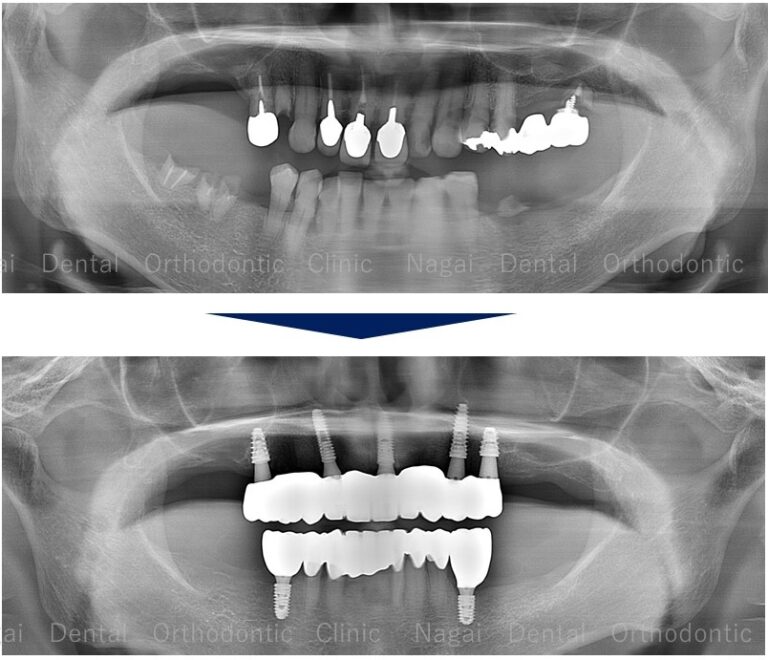

【口腔内の詳細変化】

▲再構築を目的とした治療を行いました

▲欠損していた左上奥歯部分の補綴完了状態

▲支持の安定が期待される治療を行いました

| 治療内容 | 上下オールオン4 |

| 年齢/性別 | 70代/男性 |

| 背景 | 既存補綴物の脱離と広範囲な欠損を主訴に来院。上下顎ともに「オールオン4」を採用し、骨造成を最小限に抑えつつ即日の機能回復を図りました。チタンフレームとジルコニアに加え、歯肉部分も精巧に再現することで自然な口元を構築。安定した噛み合わせにより、食事や会話を心から楽しめる日常を取り戻されました。 |

| 治療期間 | 約16か月(通院8回) |

| 費用 | 6,357,780円(税込) |

| リスク/副作用 | インプラント手術は全身状態や持病によっては適応できない場合があります。また、術後の口腔清掃を怠ると、天然歯の歯周病に似たインプラント周囲炎が起こる可能性があるため、定期的なメンテナンスが必要です。 |